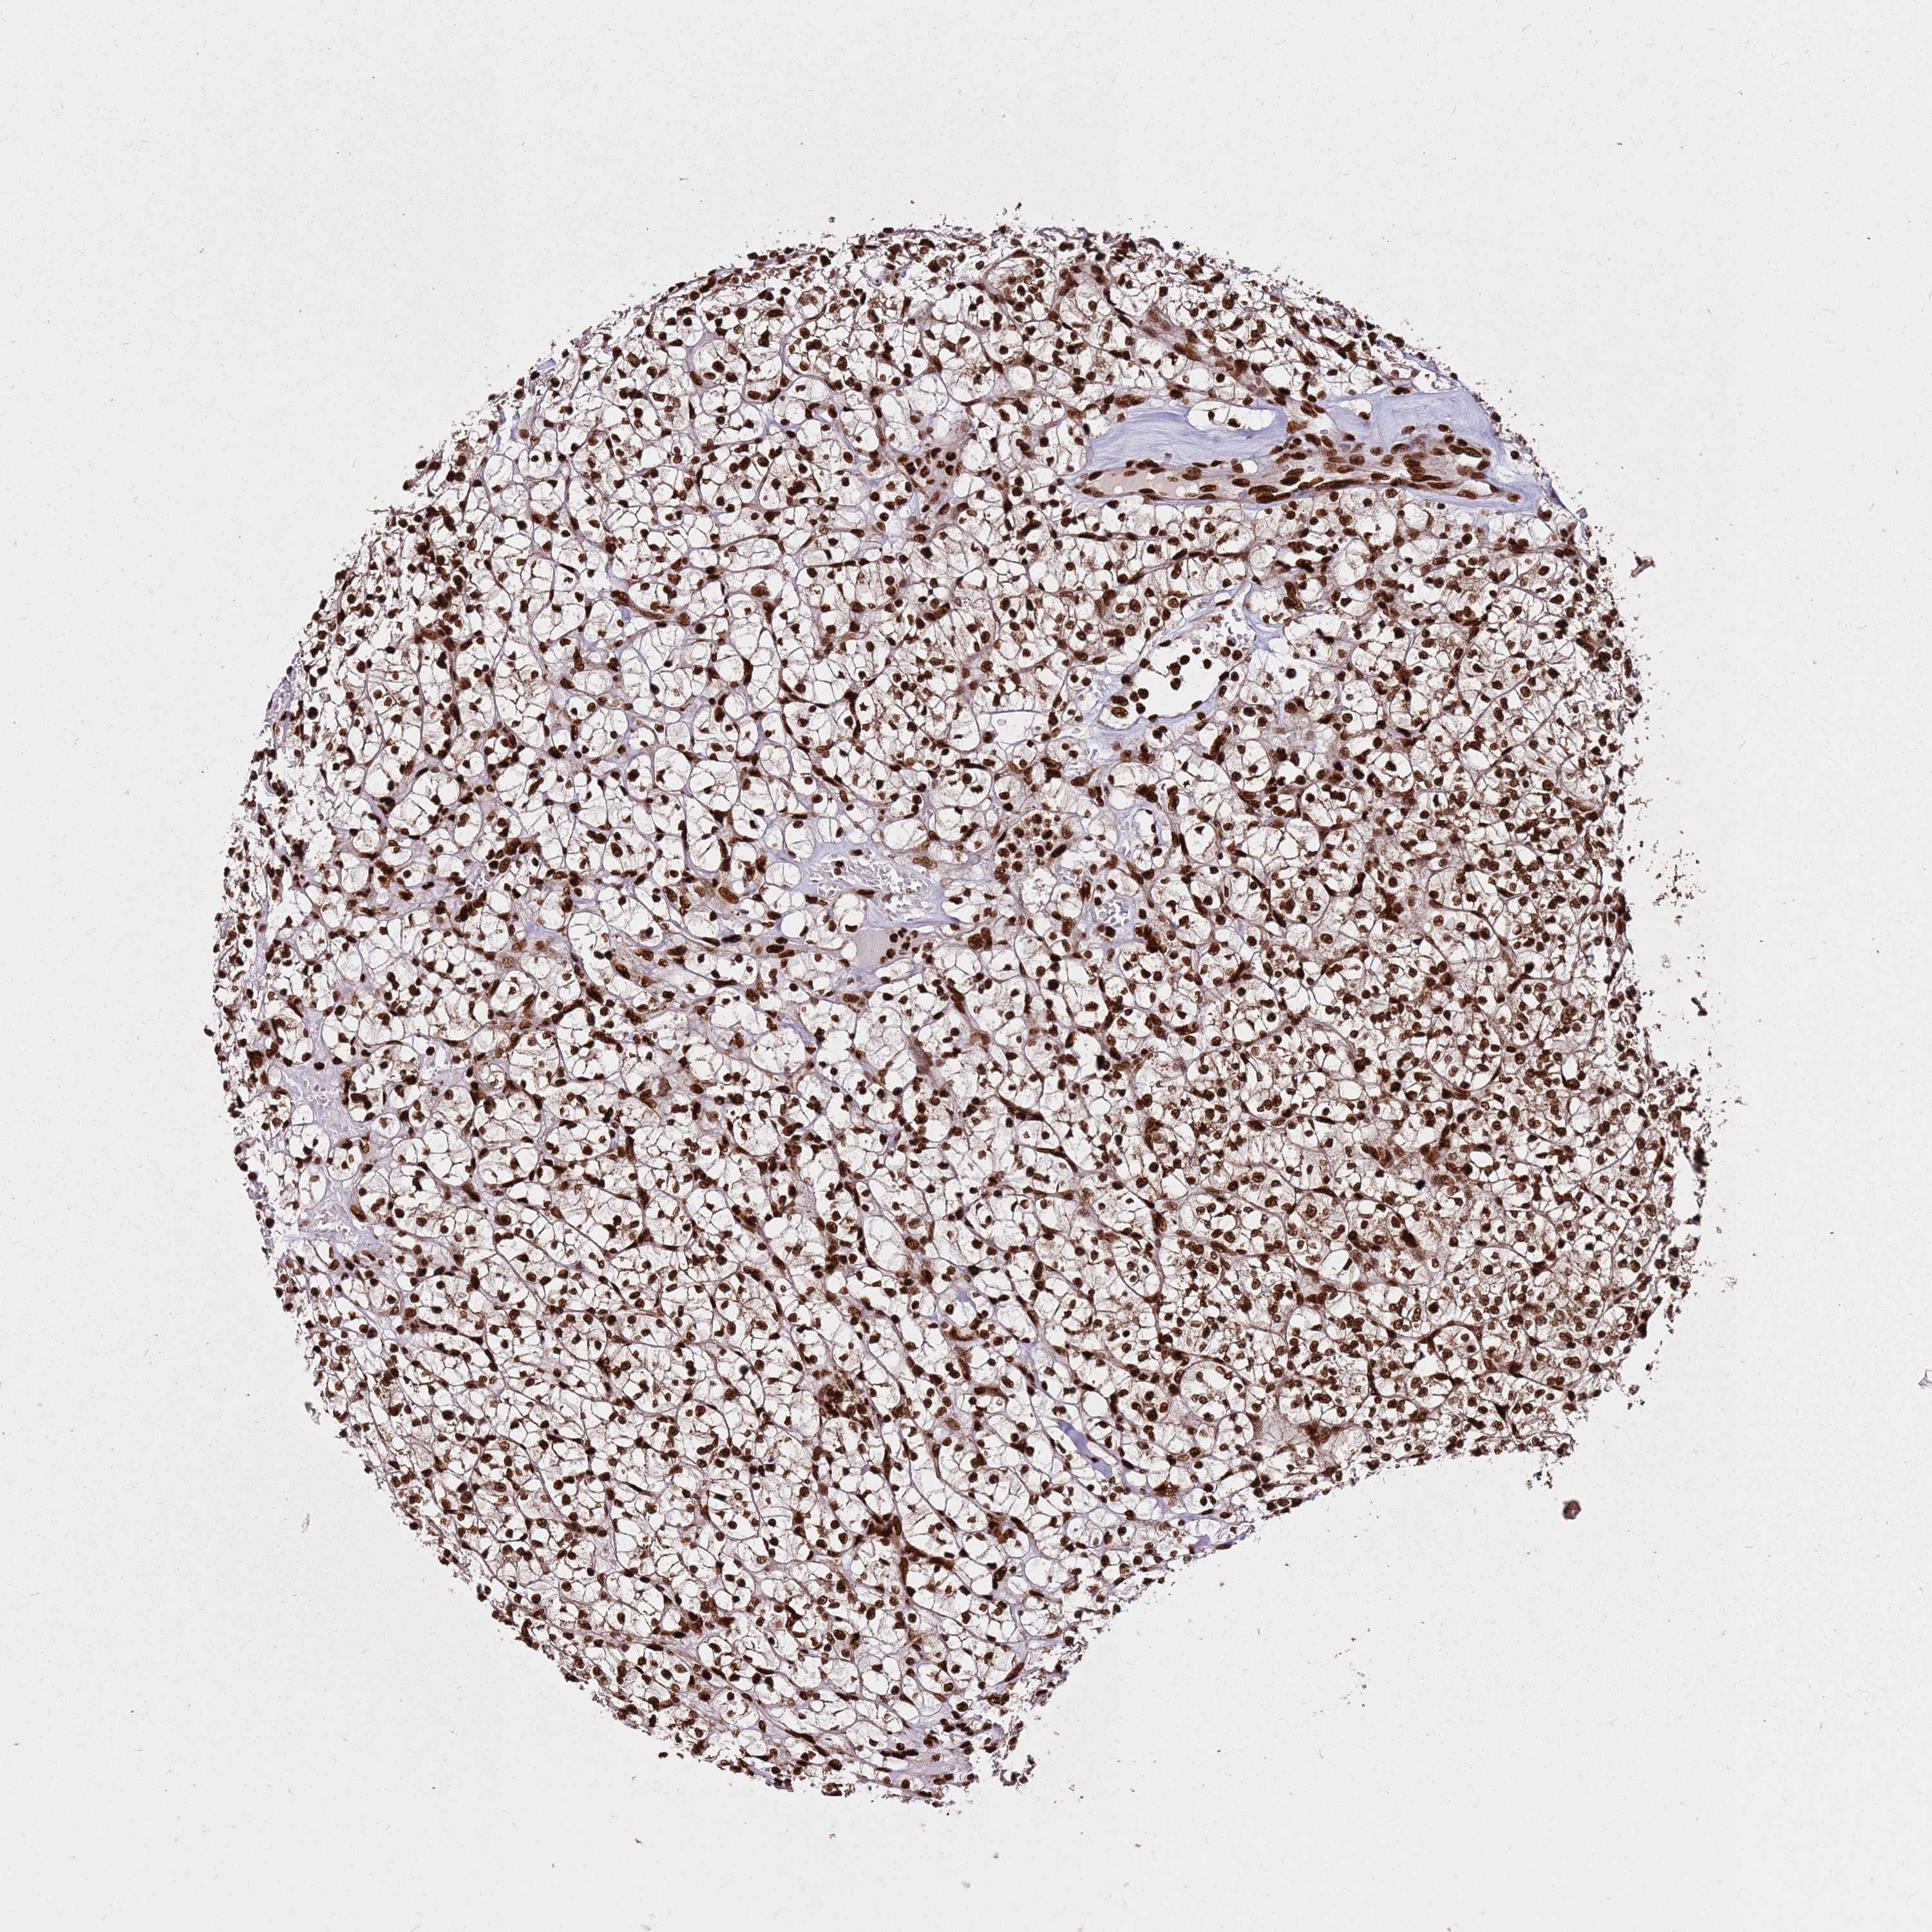

HNRNPAB is not prognostic in Kidney Renal Clear Cell Carcinoma (TCGA)

Average pTPM 94.0

Number of samples 521